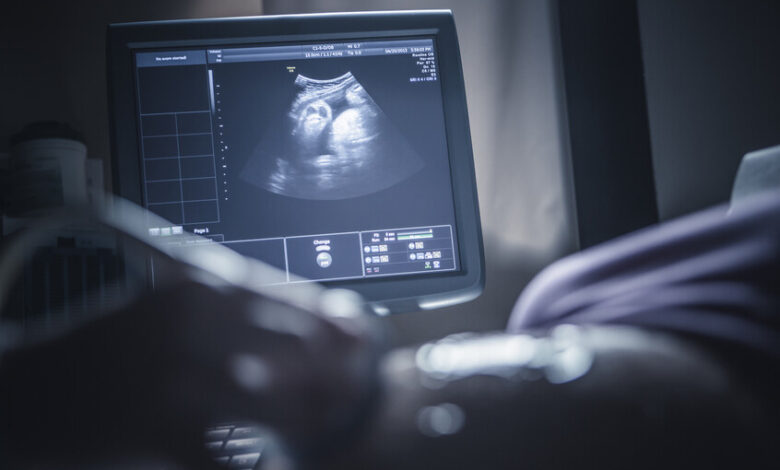

وجدت دراسة حديثة علاقة مقلقة بين تعرض الحوامل لتلوث الهواء وتباطؤ عملية نضج الدماغ لدى الأطفال حديثي الولادة.

وأظهرت الدراسة المشتركة بين مستشفى ديل مار، ومعهد برشلونة للصحة العالمية، ومركز البحوث الوبائية والصحة العامة أن تعرض الأمهات لمستويات مرتفعة من الجسيمات الدقيقة المحمولة جوا (PM2.5) أثناء الحمل يؤدي إلى تباطؤ عملية الميالينة في أدمغة أطفالهن حديثي الولادة، وهي العملية الحيوية التي تغلف الوصلات العصبية بالميالين لتعزيز كفاءة نقل المعلومات.

واعتمدت الدراسة على متابعة مجموعة من الحوامل في ثلاثة مستشفيات كبرى في برشلونة، وخضع 132 طفلا حديث الولادة لفحوصات متقدمة بالرنين المغناطيسي خلال الشهر الأول لتقييم مستوى نضج أدمغتهم عبر قياس تقدم عملية الميالينة.